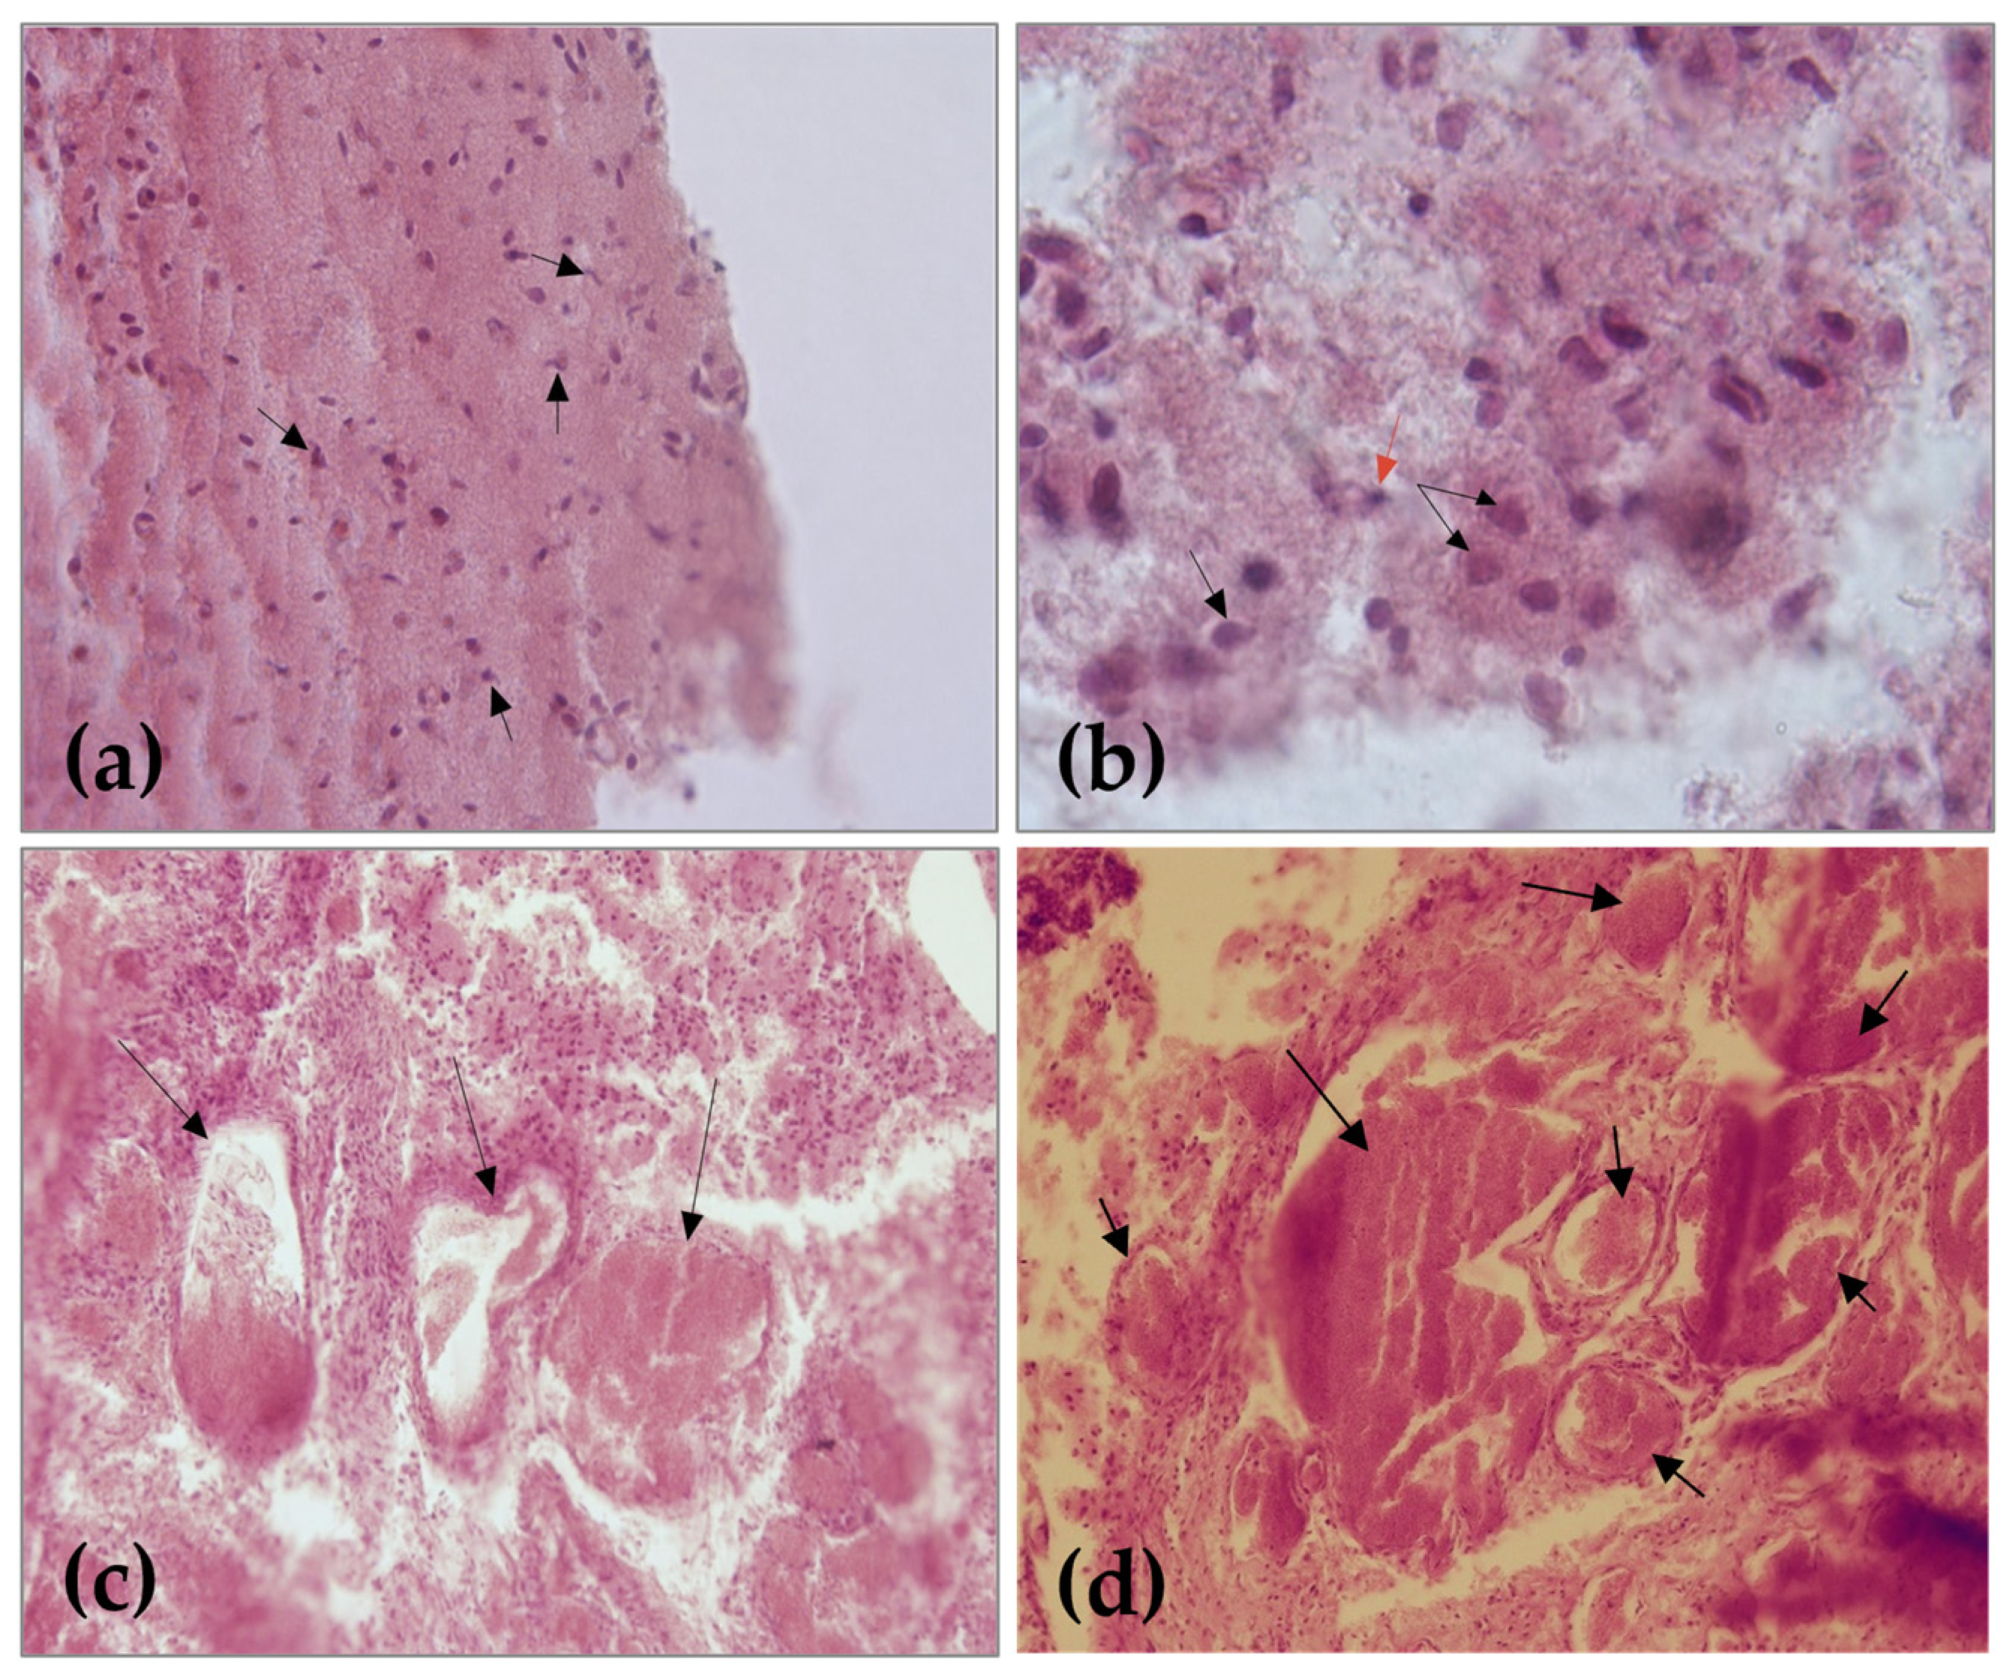

2.2. Cytohistological Investigation

3. Results

3.1. Clinical Presentation